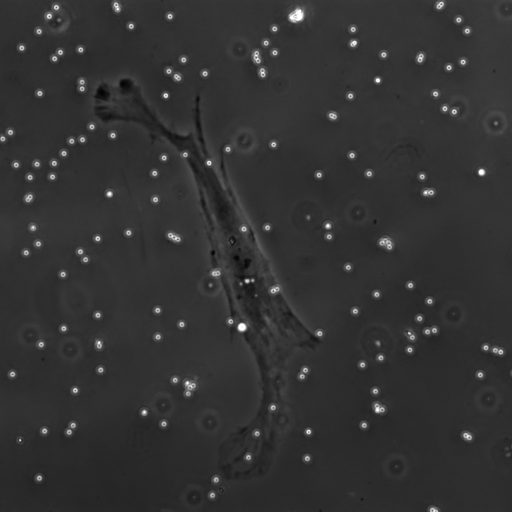

We evaluate the performance of each approach with five classical metrics: intersection over union (IoU), Dice score, precision, recall, and Hausdorff Distance (HD). We provide results on datasets , , and in Tables 1, 2, and 3, respectively. In Figure 2, we also illustrate representative segmentation results on dataset for each methods.

Raw

The original U-net model produces poor segmentation results on datasets and while performing better on dataset . CE-net performs better than U-net and results in a strong recall in all three datasets. Attention U-net outperforms both CE-net and U-net on most metrics. The Attention gates incorporated in AURA-net allow outperforming CE-net, while its pre-trained layers help improve over Attention U-net. On top of that, the AC loss provides the network with additional information on object regions. As a result, AURA-net generally outperforms competing approaches. It occasionally scores closely to Attention U-net and CE-net, and even concedes a lead on recall in datasets and and on precision in dataset . It however performs best overall, with a consistent clear advantage on the IoU, Dice, and HD metrics.

In Figure 3, we illustrate failure cases in dataset . In the first example, AURA-net fails to correctly segment the bottom part of the object. This outcome is unsurprising considering that the raw image exhibits a lower SNR than any of the training data. In the second example, the segmentation mask predicted by AURA-net contains several objects, yielding a poor overlap with the ground truth annotation featuring a single cell. However, the original image reveals the presence of a second, partially cropped non-annotated cell. In this case, part of AURA-net’s “false” detection are actually correct predictions that have been omitted in ground truth annotations.